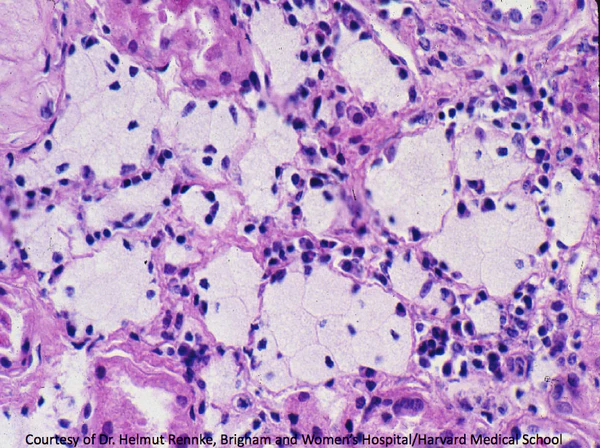

5. Биопсия почки — выявляет изменения базальной мембраны клубочков, характерные для синдрома Альпорта.